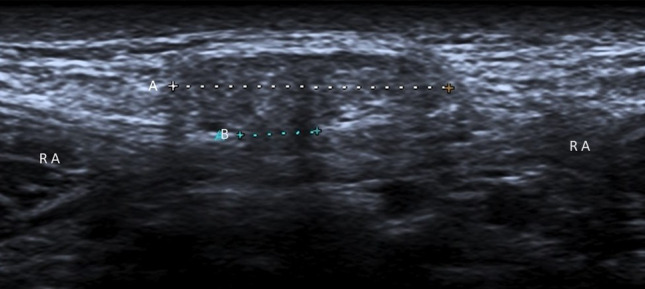

Fig. 5.

Paraumbilical hernia. Ultrasonography shows preperitoneal fat (A: caliper) through a defect (B: caliper) in the linea alba, just cranial to the umbilical cicatrix. These hernias typically occur between 35 and 50 years of age. RA rectus abdominis